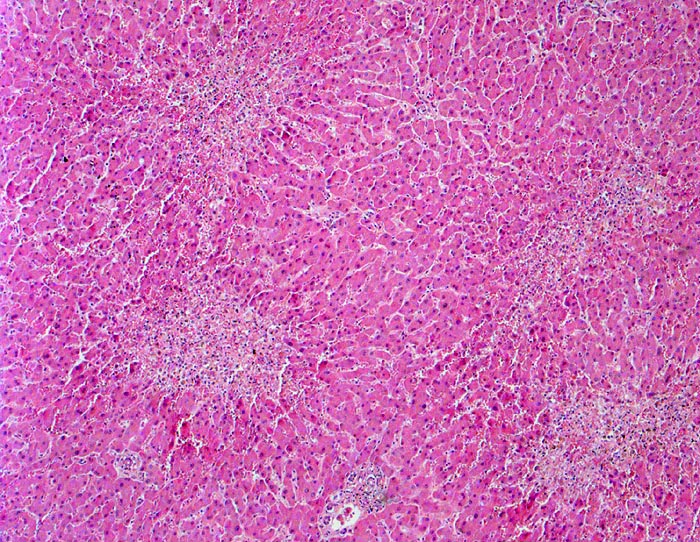

Einleitung

Linksherzversagen oder ein Schockzustand können zu einer hepatischen Minderperfusion mit ischämischen Koagulationsnekrosen der perivenulären Hepatozyten führen. Die Kombination von Hypoperfusion und retrograder Stauung (Rechtsherzversagen) führt zu zentrilobulären hämorrhagischen Nekrosen. Klinisch führen diese Nekrosen zu einer transienten geringen bis mässigen Erhöhung der Transaminasewerte, gelegentlich auch zu einem leichten Ikterus.

Metastasierendes Kolonkarzinom. Als Todesursache fanden sich nicht ganz frische zentrale und perizentrale Lungenembolien.